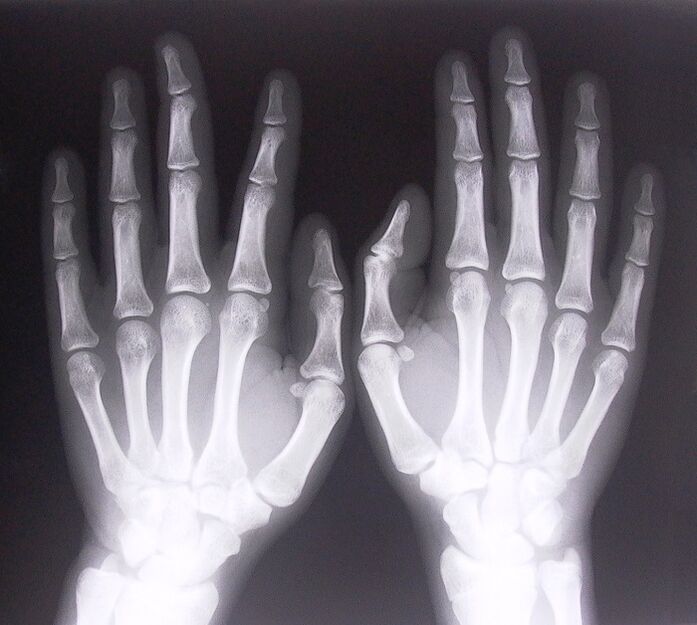

Untuk mula merawat sakit sendi di jari, anda perlu menentukan dengan betul penyakit yang menyebabkannya. Untuk menentukan jenis penyakit yang menimpa seseorang yang merasakan sakit pada sendi apabila membengkokkan lengan mereka, doktor mengesyorkan menjalani prosedur berikut:

- Ambil x-ray.